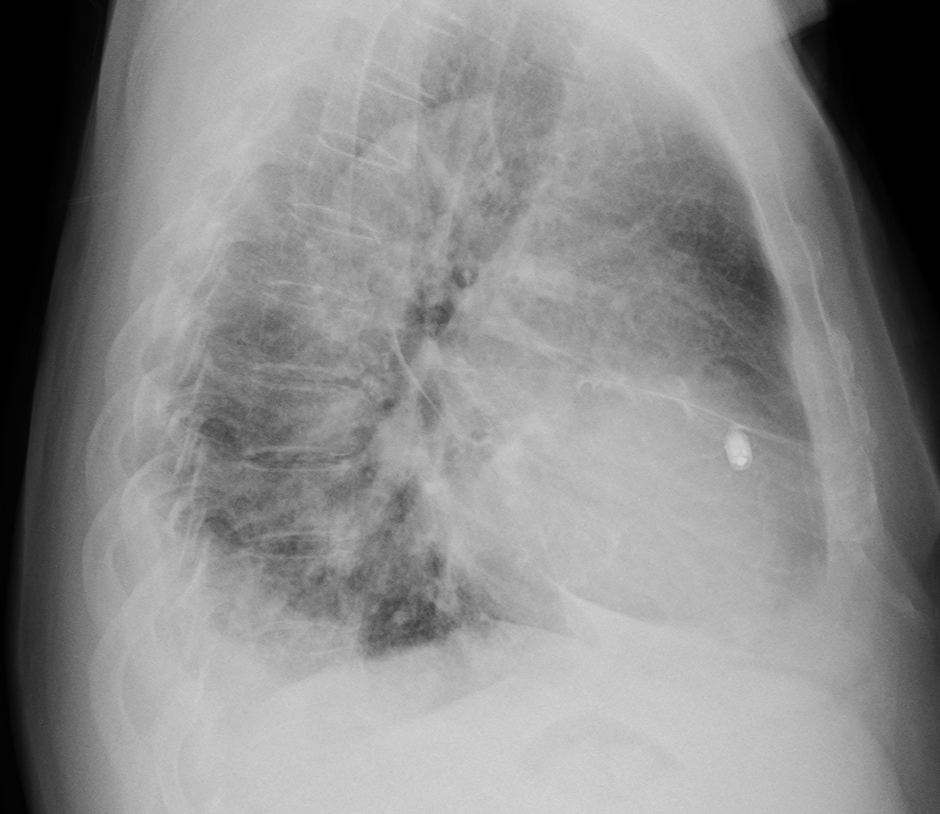

이식형 심장 사건 기록기 (Implantable loop recorder)

이식형 심장 사건 기록기 (ILR) 은 USB 메모리 스틱과 비슷한 납작한 모양의 작은 물체입니다. single-lead 심전도를 기록, 저장할 수 있는 기능을 가지고 있습니다. (최대 3년) 특정 서맥, 빈맥 부정맥이 발생할 경우 자동으로 심전도를 저장할 수 있습니다. 환자가 증상이 있을 때 추가적으로 심전도를 기록할 수 있습니다.

가장 작은 ILR 인 Reveal LINQ 는 4.48 cm x 0.72 cm 크기입니다.